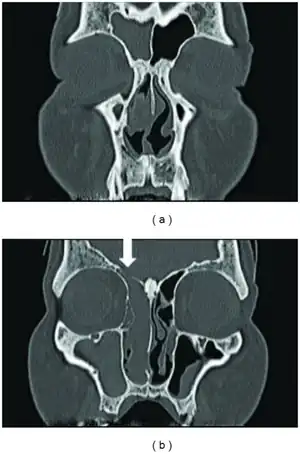

a,b)Isodense mass which occupied the right nasal cavity, maxillary, ethmoid, and frontal sinuses